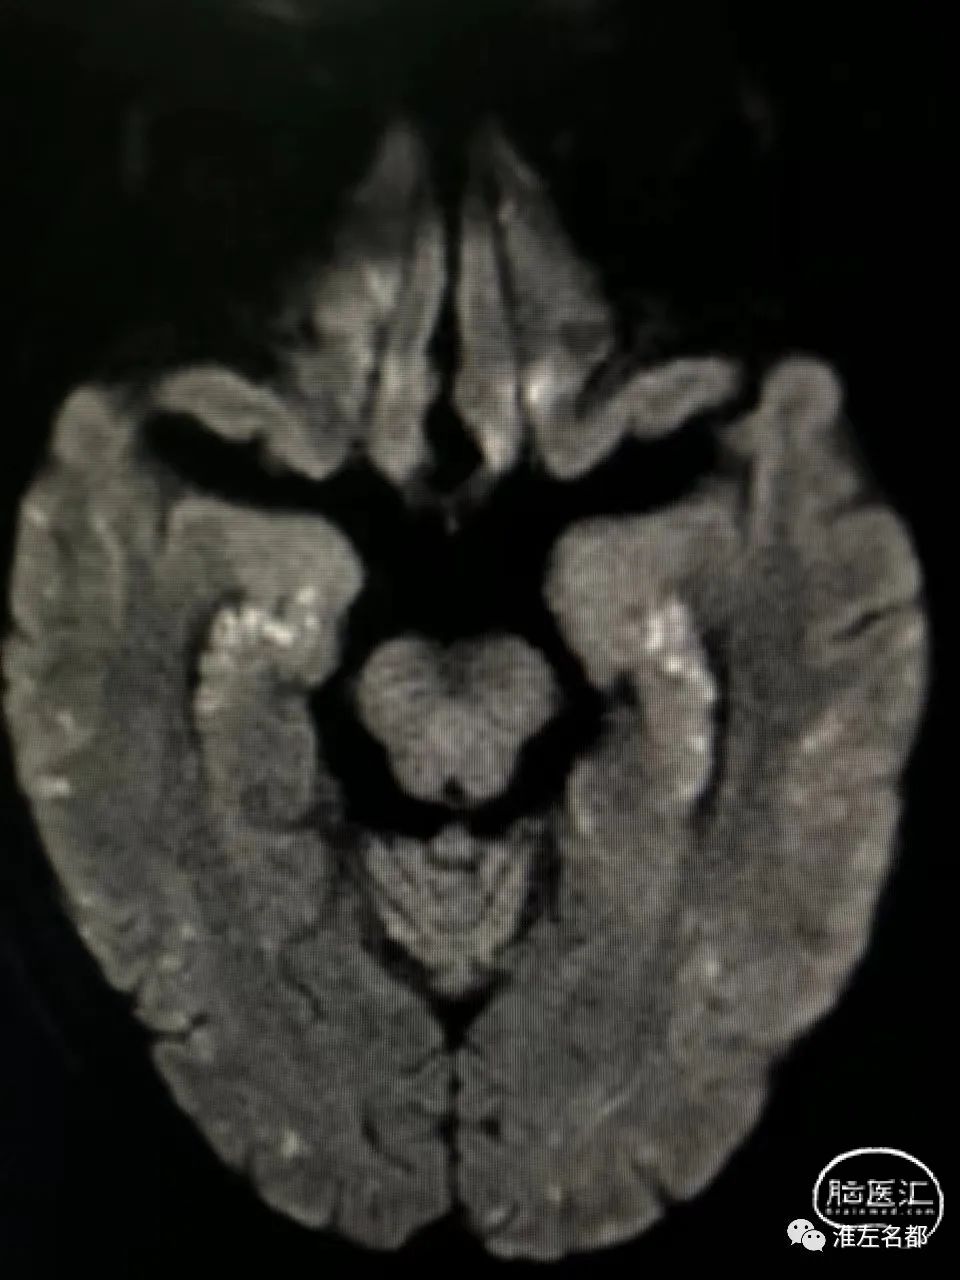

脑DWI:双侧半球皮质和皮质下弥漫分布的点状急性微小梗死灶。

第一,心源性栓塞梗死:患者心电图、心脏超声和心梗组合均提示心肌梗死,而心肌梗死是重要的心源性脑栓塞原因;该患者急性梗死病灶累及双侧半球多个脑动脉供血区,这个特征也是支持心源性栓塞的。

第二,还有一种可能的机制是,与肝癌栓塞治疗相关的反常栓塞:肝癌的肿瘤组织内是可能存在异常动-静脉瘘的,此时微小的球状介入栓塞材料就能通过这种瘘,经肝静脉进入下腔静脉和右心房,如果同时合并卵圆孔未闭,栓塞微球可经未闭的卵圆孔进入体循环,进而栓塞全身各个器官,包括脑和心脏。上述机制的支持点包括:患者53岁中年男性,而很大比率中-青年人群会合并卵圆孔未闭;患者术前无心脏疾病和心血管危险因素,术后即胸闷气促,这可能与介入用微球栓塞心肺的供血血管有关;由于微球直径很小,只会导致脑动脉远端的微小血管闭塞,所以脑梗死的范围很小,且弥漫分布。